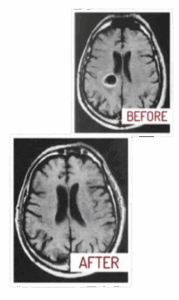

It helps address conditions like heart disease, clogged arteries, tumors, arthritis, asthma, Alzheimer’s, and even cancer.

By targeting the right meridian at the right moment, you can achieve remarkable results, restoring balance and improving overall health.

By focusing on key meridian points at the right time, you can address chronic health issues such as heart disease, arthritis, and even cancer.